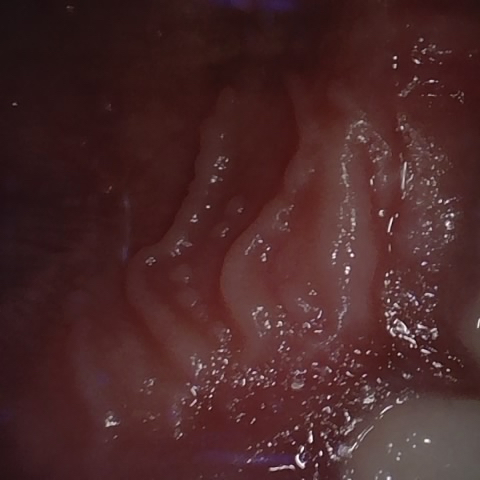

NHD39174

Overview

Annotated as "Good"